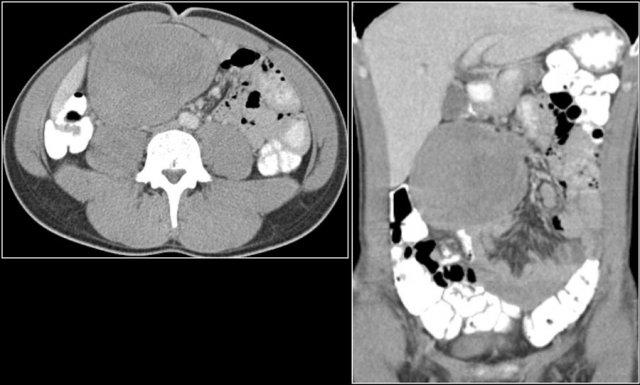

Các hình ảnh này thuộc về một bệnh nhân nhập viện với di căn phúc mạc.

Khối u nguyên phát được xác định là u carcinoid của ruột thừa.

Đây là hình ảnh điển hình của u carcinoid biểu hiện là một khối mạc treo lớn với phản ứng xơ hóa desmoplastic và co kéo các quai ruột non lân cận kèm dày thành ruột (các mũi tên).

U carcinoid có vôi hóa và phản ứng xơ hóa desmoplastic. Tắc ruột non do thành phần trong lòng ruột của u carcinoid. Lưu ý tổn thương di căn gan nhỏ (mũi tên).

Di căn của u carcinoid

Khả năng di căn có liên quan đến kích thước của khối u.

Ví dụ, tỷ lệ di căn hạch và di căn gan xấp xỉ 20-30% ở bệnh nhân có u carcinoid nhỏ hơn 1 cm, nhưng tăng lên gần 60-80% đối với di căn hạch và 20% đối với di căn gan khi khối u có kích thước 1-2 cm.

Ở bệnh nhân có khối u nguyên phát lớn hơn 2 cm, tỷ lệ di căn hạch là 80% và di căn gan là 40-50%.

Di căn gan thường có tính chất tăng sinh mạch và có thể có hoại tử trung tâm.

Hầu hết các di căn hạch bạch huyết đều có vôi hóa, tương tự như khối u nguyên phát.

Cùng bệnh nhân.

Bốn năm sau lần chụp CT ban đầu, ghi nhận nhiều tổn thương di căn gan.

Lưu ý kiểu ngấm thuốc tăng sinh mạch trong thì động mạch muộn.